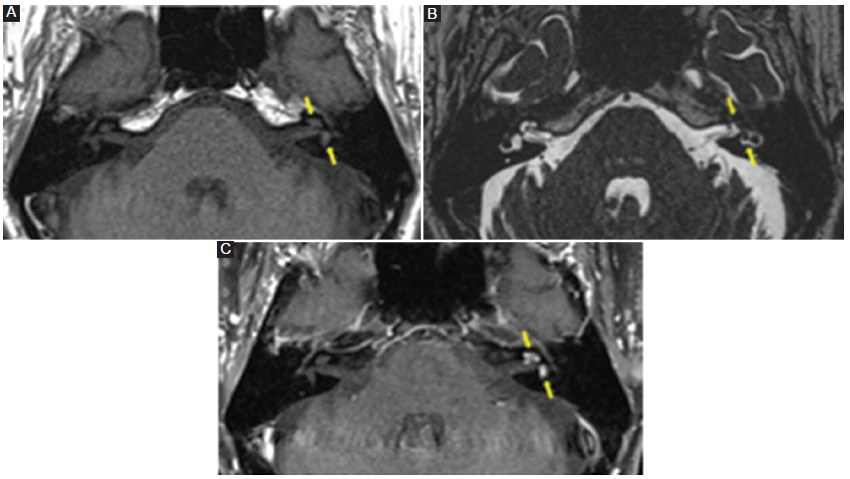

Todos los pacientes con neurinoma intralaberíntico revelaban una baja señal en la secuencia T2 AR, ligera hiperseñal en la secuencia T1 SC y realce poscontraste con márgenes bien definidos (Fig. 3). Tres pacientes con laberintitis inflamatoria (42,5%) mostraron baja señal en las secuencias T2 AR y T1 SC, y 5 pacientes (71%) manifestaban realce con el contraste (Fig. 4), con márgenes menos claros que los pacientes con neurinoma. Los 5 pacientes con laberintitis osificante presentaron baja señal en la secuencia T2 AR, y 2 pacientes (40%) tenían hiperseñal en la secuencia T1 SC (Fig. 5). Solo en 3 pacientes con laberintitis osificante se realizó secuencia con contraste, y 2 de ellos mostraron realce. Los 3 pacientes con hemorragia evidenciaron una señal alta en la secuencia sin contraste (Fig. 6) y 2 (66,7%) presentaron refuerzo poscontraste (Tabla 2).

Característicamente, por RM suelen mostrar una señal ligeramente hiperintensa en la secuencia T1 SC y un marcado realce focal en la secuencia T1 CC. Algunos casos infrecuentes pueden tener solo un ligero realce, pero acompañan una clara ausencia de señal en la secuencia T2 AR.

En los pacientes analizados en nuestra investigación, el 100% presentaron las tres características clásicas mencionadas en la literatura: alta señal en la secuencia sin contraste, ausencia de señal en la secuencia T2 AR y marcado realce con el contraste5,6.